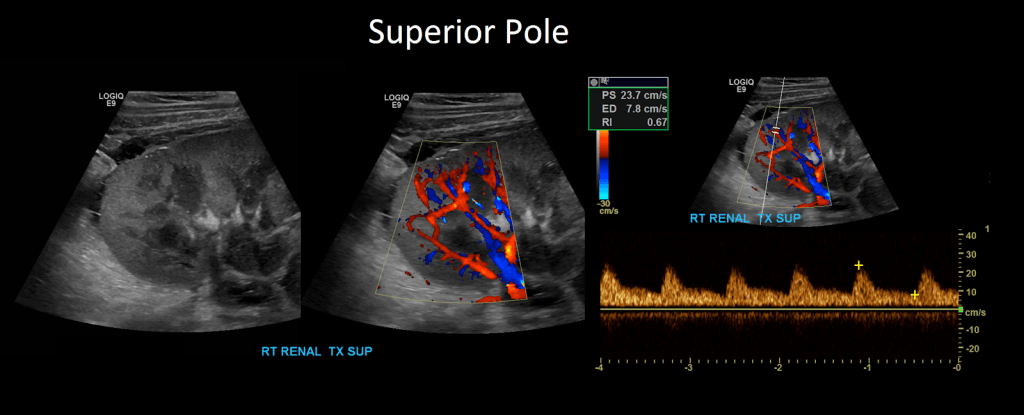

Once that is complete move on to Doppler the arcuate/segmental arteries (your institution may require one or the other or both). Doppler these arteries in the superior, mid and inferior pole of the kidney. Do not use angle correction.

Measure the peak systolic and end diastolic velocity. Resistive Index is normally between 0.50 and 0.70. The waveform should be a low resistance waveform with forward flow throughout the cardiac cycle. Take Doppler samples at the anastomosis/proximal section (pay close attention here look for aliasing to detect anastomotic stenosis), the mid and distal portions as well. If there’s any aliasing along the vessel take spectral Doppler samples there too.